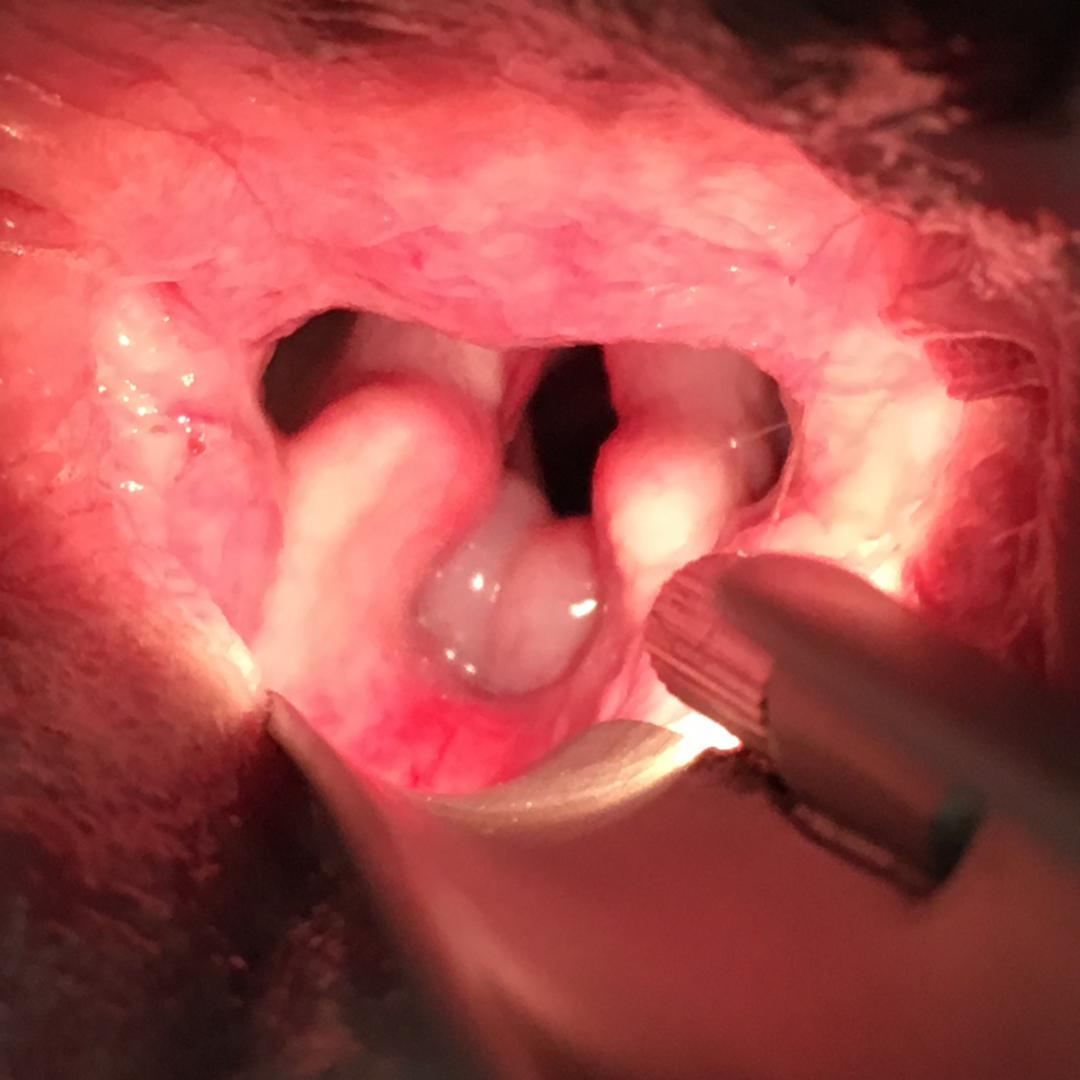

Exploration gorge: Elongation du voile

Exploration de la gorge: élongation du voile du palais qui recouvre l'entrée du larynx. Il faut aussi observer la forme et la mobilité des cartilages aryténoïdiens, évaluer la taille des amygdales et la gêne occasionnée par les diverticules laryngés s'ils sont présents.